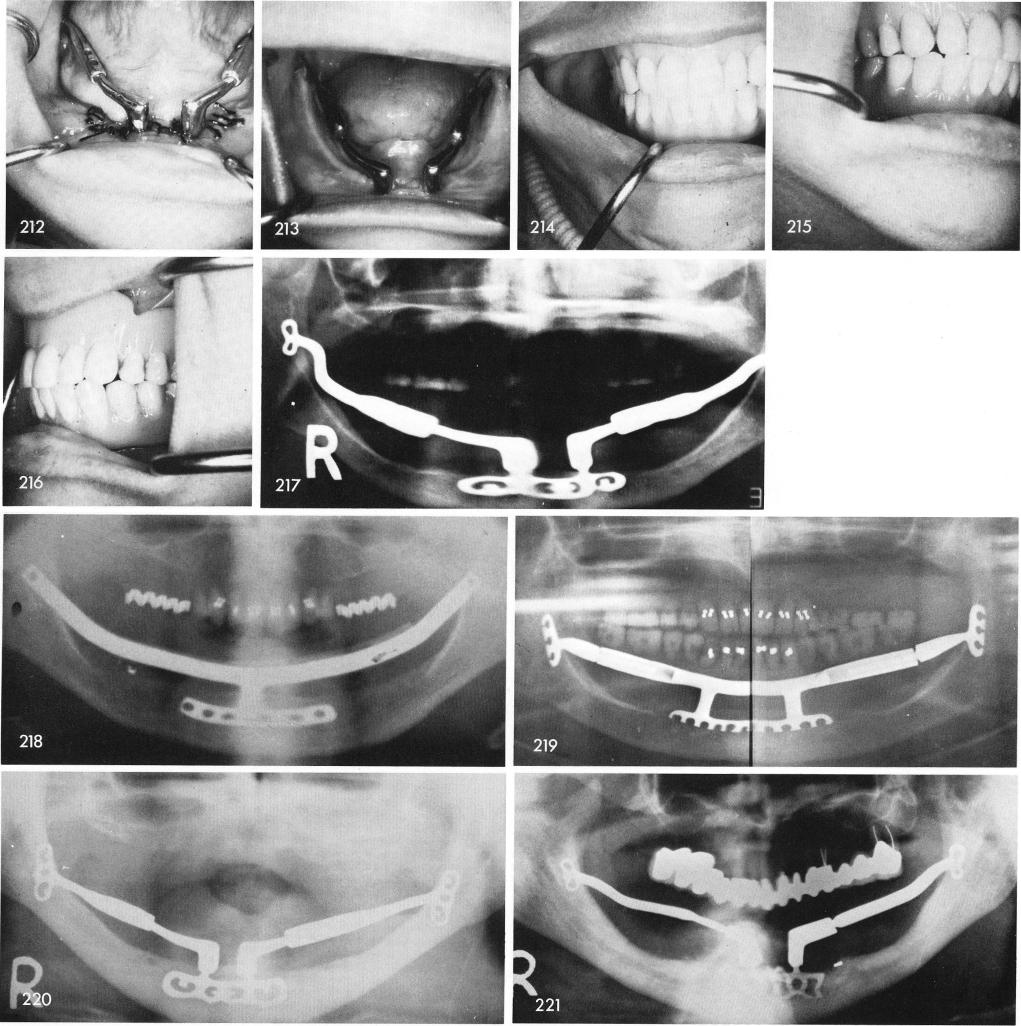

Fig. 218 shows the x-ray of original single frame ramus implant. Fig. 219 shows the x-ray of three piece ramus type implant. Figs. 220 through 230 shows the five piece system, RZS5. Fig. 231 shows x-ray of how the sliding cable saved the remaining portion of a subperiosteal. Other cases follow.

1 X ray of single frame ramus type mandibular implant